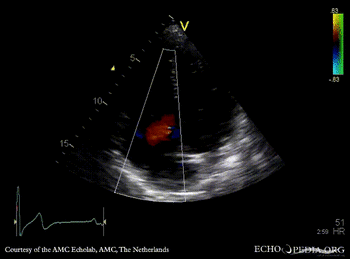

E00382.gif

A4CH: diastolic tricuspid regurgitation